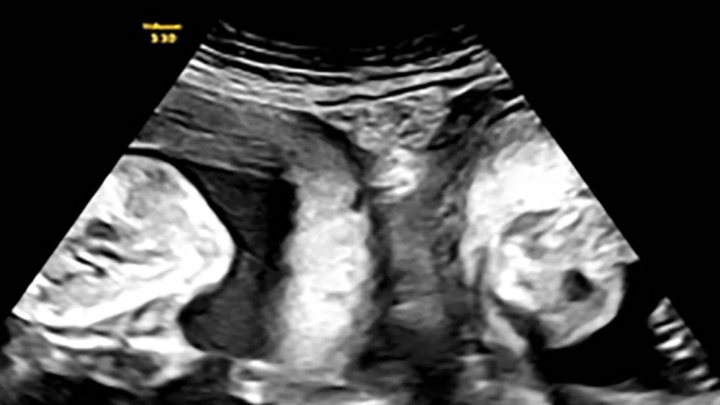

Two Uteruses

Woman with double uterus pregnant with a child in each at the same timeKelsey Hatcher has known since she was a teen that she was born with two uteruses, but never expected to get pregnant in both simultaneously.LifestyleNov 14, 2023